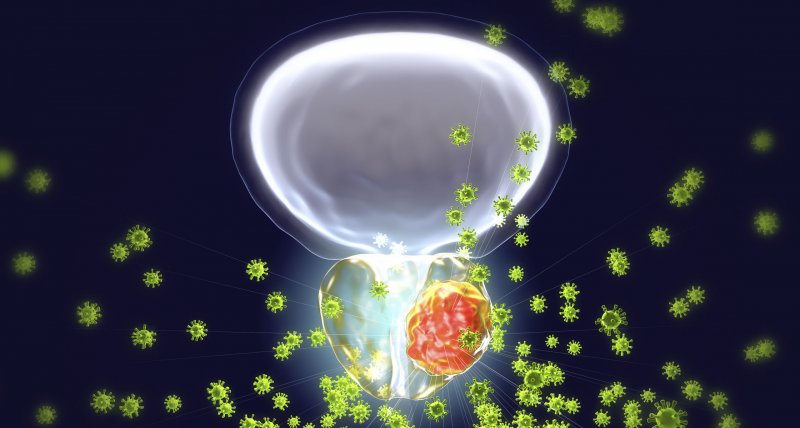

Radium-223 ists ein Kalzium-Mimetikum, das Alphastrahlen aussendet und selektiv in Knochenmetastasen eingelagert wird, wo es DNA-Doppelstrangbrüche in den Tumorzellen induziert. In Kombination mit Abirateron konnte Ra-223 weder das ereignisfreie Überleben ohne Skelettereignisse noch das Gesamtüberleben verlängern, war aber mit einer Erhöhung des Frakturrisikos assoziiert (Lancet Oncol 2019, DOI: 10.1016/S1470-2045(18)30860-X).

Die European Organization for Research and Treatment of Cancer (EORTC) hat nun zusammen mit einer Reihe weiterer Studiengruppen in Europa, Kanada und Brasilien die Phase-3-Studie PEACE-3 durchgeführt: Darin wurden 446 Patienten mit metastasiertem kastrationsresistenten Prostatakarzinom und asymptomatischen oder leicht symptomatischen Knochenmetastasen randomisiert, Enzalutamid mit oder ohne Ra-223 (55 kBq/kg alle 4 Wochen für 6 Zyklen) zu erhalten.